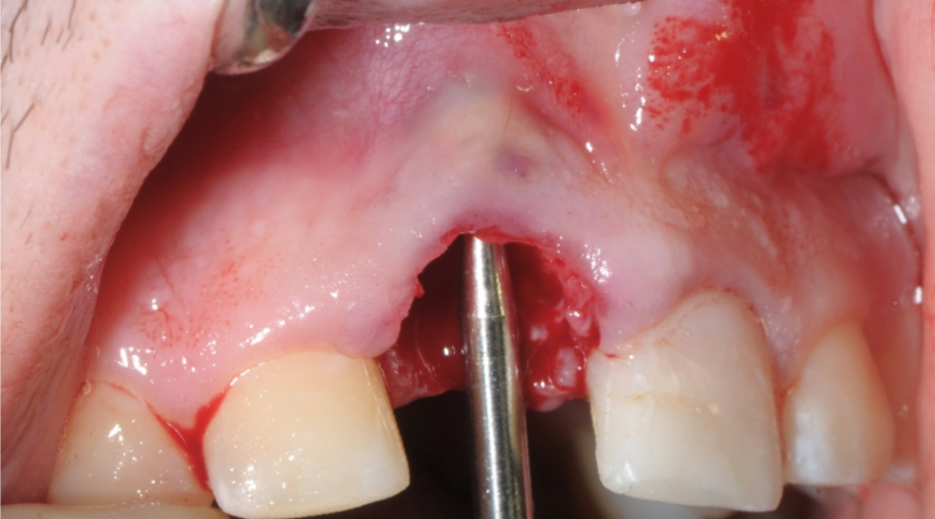

Evidenza clinica della mancanza di parete vestibolare